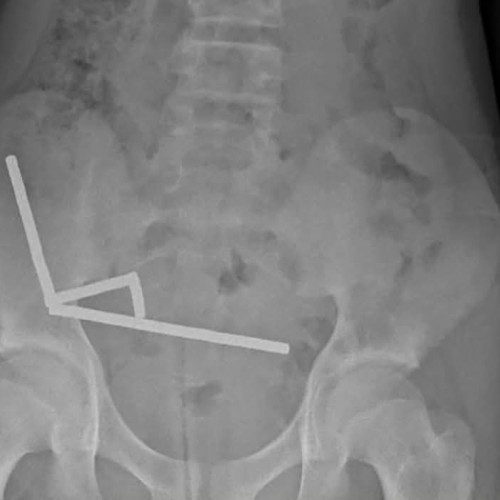

Un băiat de 13 ani din Noua Zeelandă a fost internat în spital după ce a înghițit între 80 și 100 de magneți puternici. Acesta a stat aproape o săptămână fără să ceară ajutor medical, în ciuda simptomelor îngrijorătoare. Situația a atras atenția autorităților sanitare locale.

În urma examinării și intervenției chirurgicale, medicii au fost nevoiți să îndepărteze o parte a intestinului pacientului, afectată grav de corpul străin. Intervenția s-a impus pentru a preveni complicații majore care îi puneau viața în pericol. În acest caz, timpul a jucat un rol crucial.